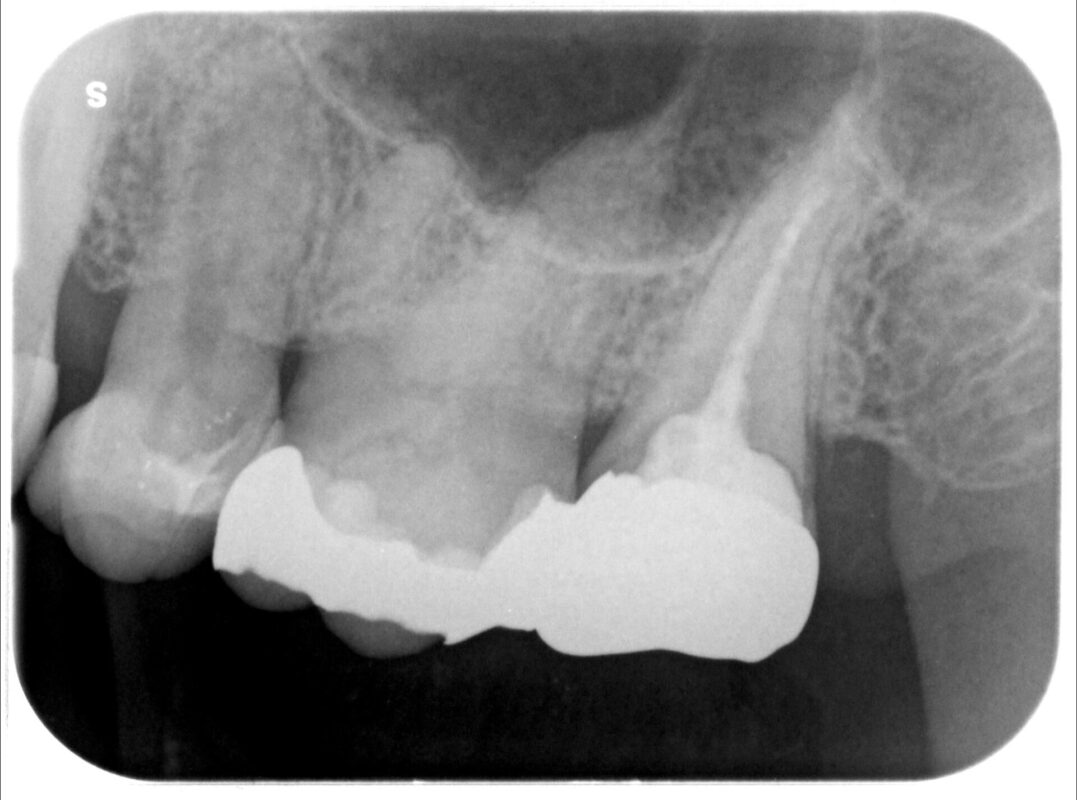

比較的最近治療されたそうですが、クラウンの下に何やら影が、、、、、、、

クラウンを除去すると案の定虫歯の取り残しがありました。

歯肉の深くまで虫歯が進行しており、それらが除去できていない状態でクラウンが処置されていたよう

です。

また、レジンコアが装着されていましたが、このような深い部分に防湿下でレジンコアを接着させるこ

とは事実上無理です。

そこを無理して行ったため、接着不良で隙間からまた感染し、虫歯が余計に深くなったと推察されま

す。